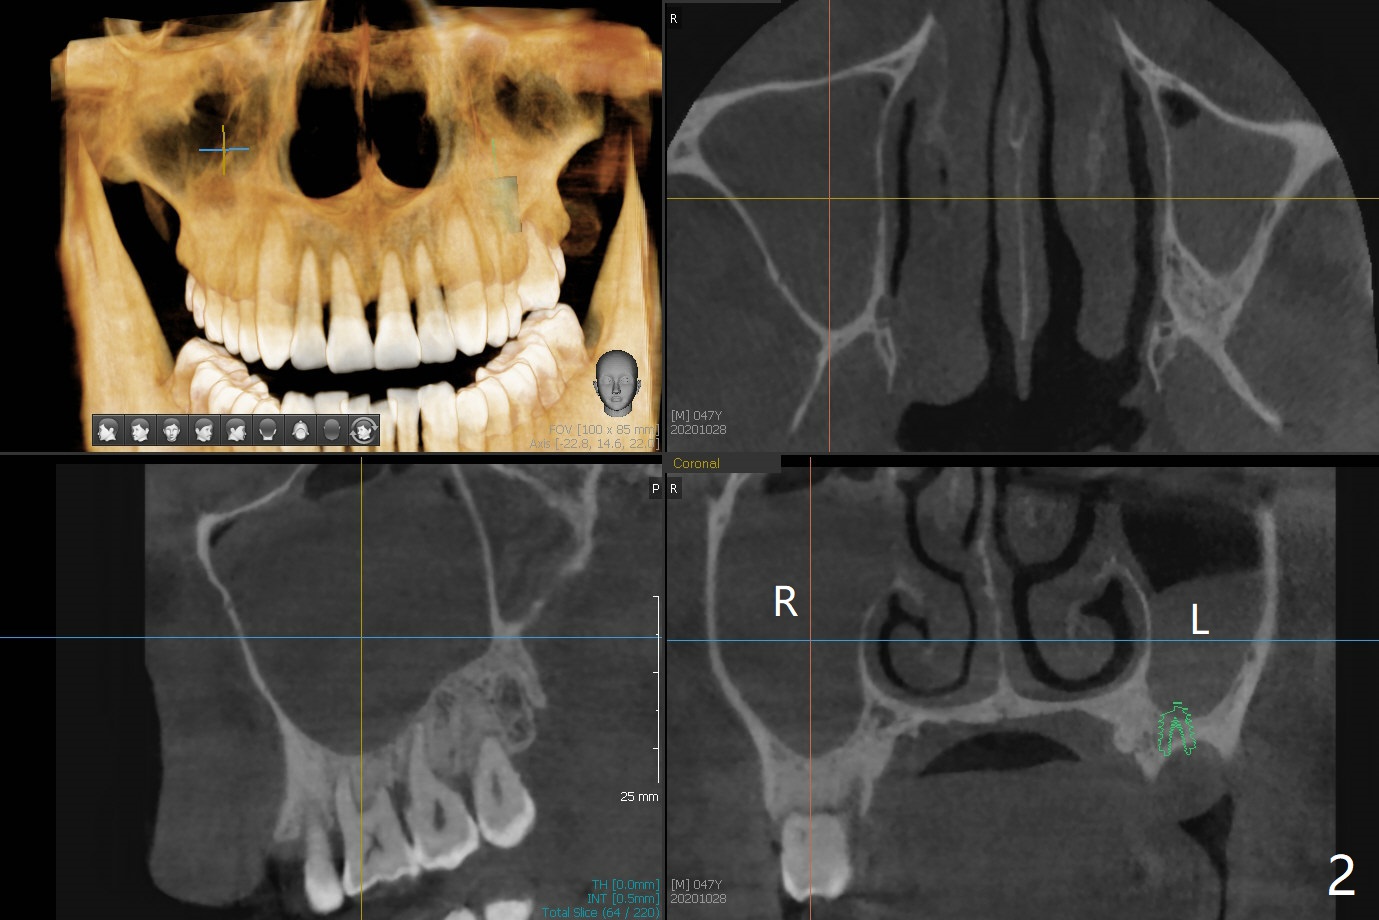

47岁男(吸烟一天半包)因右下8疼痛就诊,口服抗生素疼痛消失,不愿意拔除,但是要求左上6植牙(图一),左上颌窦好像有粘液囊肿(图一,三:*),而右侧上颌窦粘膜更厚(图二)。左上6植牙床是一个斜面,植牙会远中偏移,导板设计应有意往近中(图三:红线)。植体远中根尖需要内提升,冠部需要植骨(图四),厚的粘骨膜有利于植骨(粘骨,使用mill abutment),骨粉尽可能放置7牙根近中(图五:红色圆圈,Endogain)。第二种设计(图六)使用细长植体,近中龈下4毫米,远中龈下8毫米,有利于植骨,覆盖远中暴露的螺纹。Return to No Caries 位点保存/导板 手术 提升 Xin Wei, DDS, PhD, MS 1st edition 10/28/2020, last revision 04/04/2021